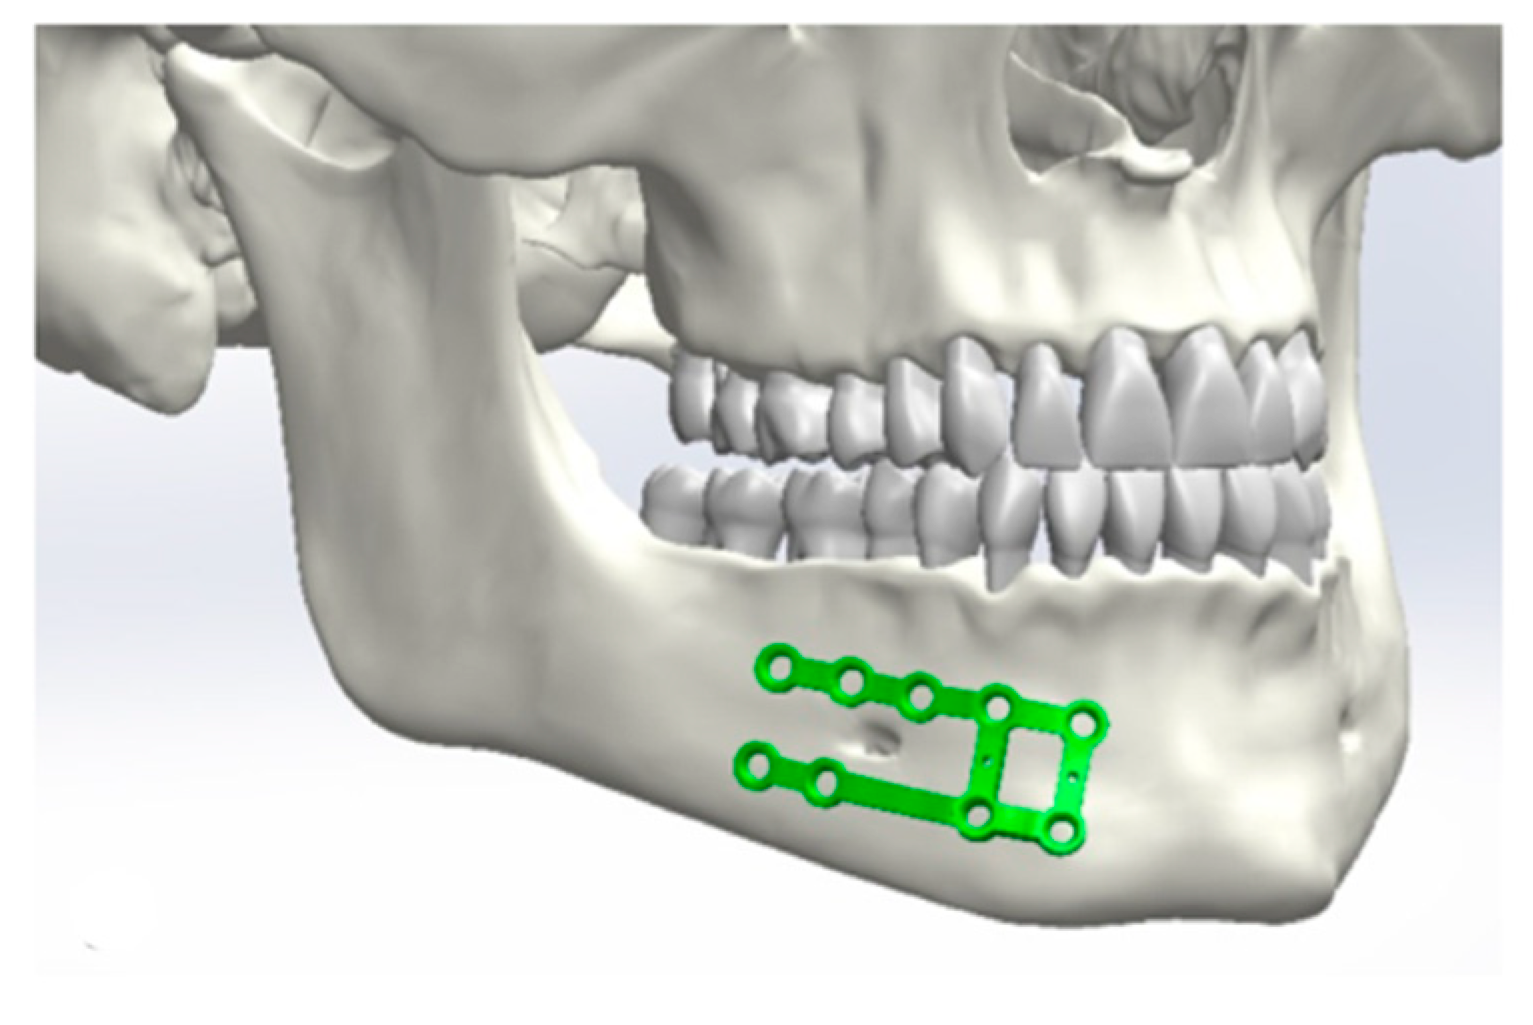

2.1. Design of the Plates

Application of the Plates